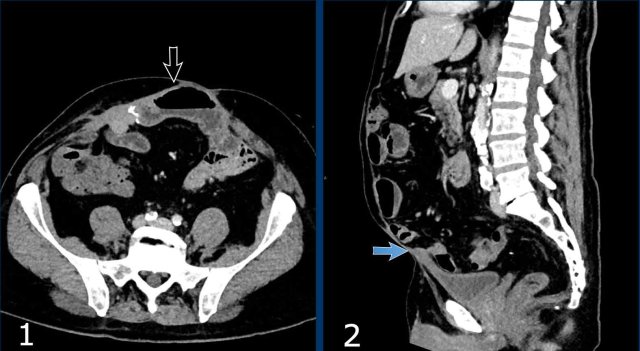

These images are of a 78 year old morbid obese female who has an incisional midline hernia.

Study the images and then compare to the next images, who were taken one month later, when she presented with a painfully swolen hernia.

Now there are signs of strangulation namely:

• New small bowel feces sign, best see on the transverse images (white arrow).

• Infiltration of mesenteric fat (black arrow).